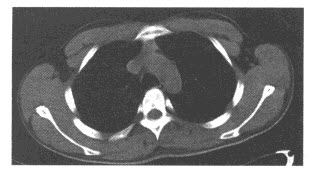

B.肾盂癌

男,58岁,头痛、恶心、行走不稳,肺和脑CT检查如图,最可能的诊断为()

A.星形细胞瘤

B.脑脓肿

C.肺癌脑转移

D.脑膜瘤

E.脑梗死